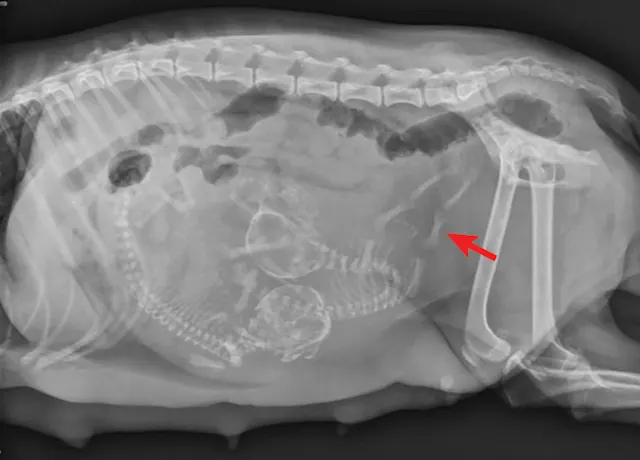

FIGURE 1

Ventrodorsal abdominal radiograph of a pregnant bitch presenting for dystocia. Note the malpositioned fetus oriented transversely to the pelvic canal. Radiographs courtesy of Amanda A. Cavanagh, DVM, DACVECC

If the bitch is examined after day 44 of gestation, when fetal skeletons mineralize, radiographs should be obtained to determine litter size, fetal positioning, and signs of fetal death.2,8 (See Figure 1 & Figure 2.) Ultrasonography is the ideal imaging modality for determining fetal stress and viability.2